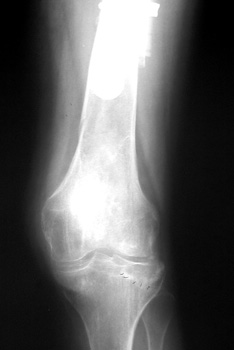

Insufficiency fracture lateral tibial plateau in patient with long revised left femoral stem